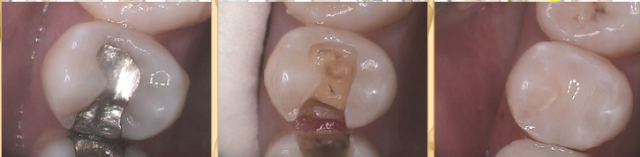

I have a few different composites in my office depending on the location, size, and expectations of outcome on the tooth. I use Sonicfill when there isn’t a lot of discoloration on the tooth, because it’s too translucent to mask amalgam staining well. I use Estelite Omega in some cases and Venus Diamond in others. I always layer when I’m not using a bulk composite — and even when using a bulk composite, I find that you have to condense repeatedly to avoid air bubbles.